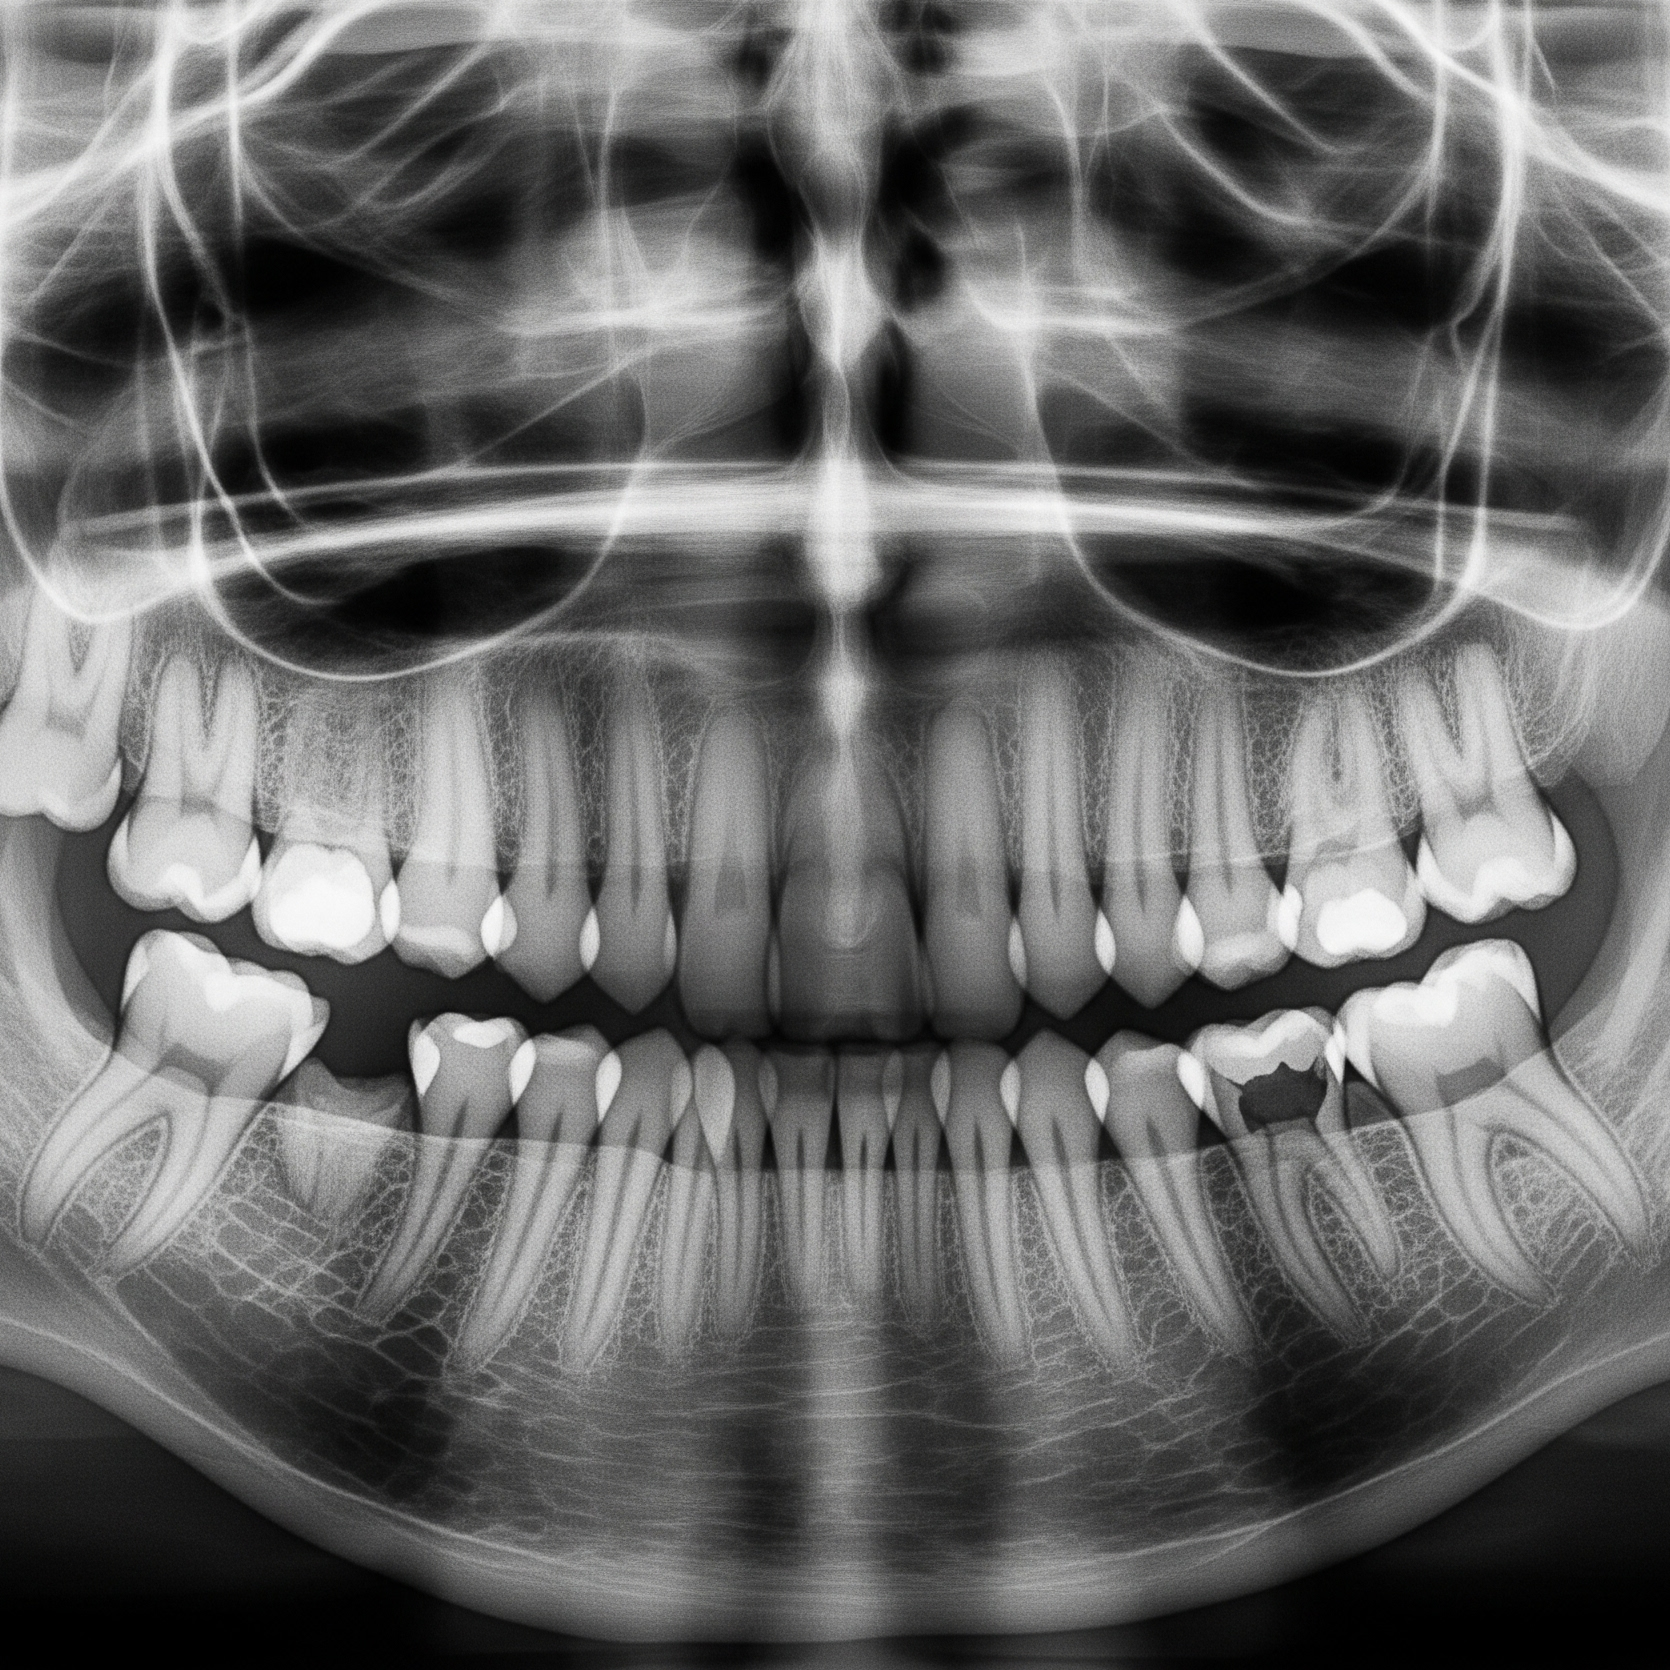

We provide gentle cleanings and exams to keep your child’s smile healthy, along with fluoride treatments and protective sealants that help prevent cavities before they start. Our digital X-rays use low radiation and allow us to monitor growth safely. Together, these preventive services give kids strong, healthy teeth and parents peace of mind.